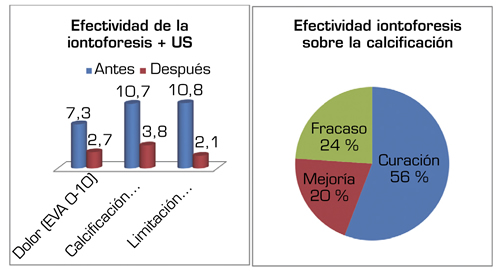

Average initial pain 7.3 points (VAS scale), significantly decreased (p = 0.0000) post treatment to 2.7. Initial average size of calcifications 10.7 mm and significantly decreased (p = 0.0000) post treatment to 3.8 mm. Change of calcification: success/cure rate 55.7 % (n = 77), improvement rate 20.2 % (n = 28); failure rate 23.9 % (n = 33). Functional limitation decreased from 10.8 % of patients to 2.1 %.

Resultados: Edad media: 54,6 años (n = 138); mujer (73,1 %; n = 101); proporción mujer/hombre 3: 1; tendón supraespinoso (94,6 %; n = 124); subescapular (5,4 %; n = 14); hombro izquierdo (55,1 %; n = 76), hombro derecho (44,9 %; n = 62); bilateral 1,4 % (n = 2); diestros 96,3 % (n = 133); antecedentes personales: tabaquismo (19,5 %; n = 27), diabetes (7,2 %; n = 10). El tiempo de enfermedad promedio fue de 6,08 meses. Dolor agudo-subagudo (menos de 3 meses) 47,1 %; (n = 65), dolor crónico (más de 3 meses) 52,9 % (n = 73). Tipo radiológico: formativo 75,3 % (n = 104), resortivo 24,7 % (n = 34). Número promedio de sesiones: 20. Complicaciones del tratamiento 2,8 % (n = 4): intolerancia/eritema/quemadura. Ocupación: administrativo 39,8 % (n = 55), trabajos manuales 60,2 % (n = 83). El dolor inicial EVA de 7,3 puntos disminuyó significativamente (p = 0,0000) después del tratamiento a 2,7. El tamaño promedio inicial de las calcificaciones fue de 10,7 mm y disminuyó significativamente (p = 0,0000) después del tratamiento a 3,8 mm. Cambio de calcificación: tasa de éxito/curación 55,7 % (n = 77), tasa de mejora 20,2 % (n = 28); tasa de fracaso del 23,9 % (n = 33). La limitación funcional disminuyó de un 10,8 % a un 2,1 %.

El dolor inicial promedio era de 7,3 puntos en la escala EVA, y disminuyó significativamente (p = 0,0000) postratamiento a 2,7 puntos (Figura 3). El tamaño inicial promedio de las calcificaciones era de 10,7 mm y disminuyó significativamente (p = 0,0000) postratamiento a 3,8 mm (Figura 3).

Fig. 3. Efectividad de la iontoforesis sobre el dolor (EVA 0-10), el tamaño de la calcificación (mm) y la limitación funcional (%) en los pacientes con tendinitis calcificante del hombro.

El cambio de calcificación es considerado una variable de resultado, la cual consideraba la desaparición (disminución de más del 75 %), disminución (reducción entre el 25-75 %) o no (reducción de menos del 25 %) de la calcificación. Esto nos permite evaluar al tratamiento como éxito/curación, mejoría o fracaso, respectivamente. Esto supuso una tasa de éxito/curación del 55,7 % (n = 77), mejoría del 20,2 % (n = 28) y un fracaso del 23,9 % (n = 33) (Figura 3).

Tras el tratamiento, de 15 pacientes con limitación funcional (10,8 %), solo 3 (2,1 %) permanecieron con limitación, por lo que requirieron terapia manual (20 sesiones en promedio) para su recuperación completa (Figura 3).